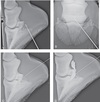

In advanced cases, a circular lytic area in the distal phalanx can be recognized radiographically (see Figure 91-16, B). This area should not be mistaken for the naturally occurring toe crena at the dorsal aspect of the distal margin of the distal phalanx. Often, a sclerotic border delineates the lytic area (see Figure 91-16, B)

Figure 91-16. (A) Photograph of the sole of a foot with a keratoma showing focal chronic infection near the toe. (B) Dorsoproximal-palmarodistal oblique radiographic view of the same hoof showing a lytic area in the distal phalanx extending proximally along the hoof wall (surrounded by arrows), which is characteristic of a keratoma.